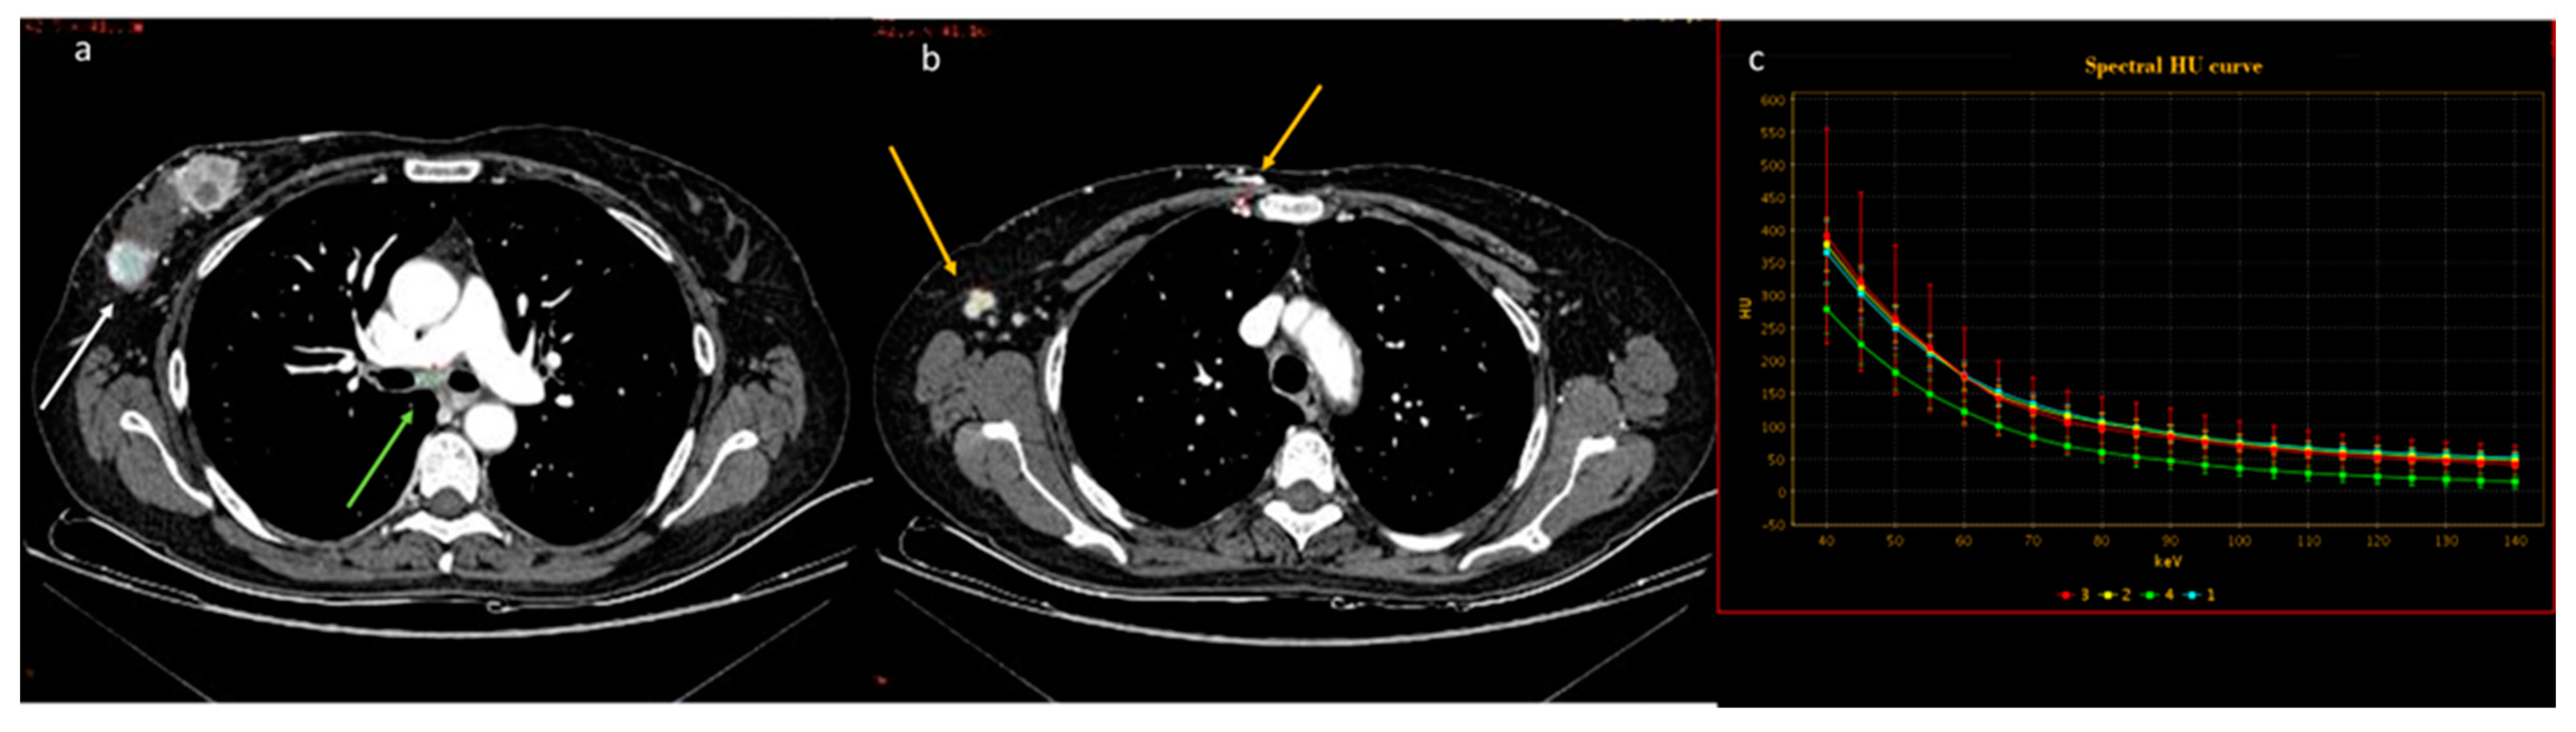

| Sato et al. [48] Retrospective study | Japan | To compare the utility of ringlike peripheral increased IC and conventional findings for differentiating primary lung cancers from pulmonary metastases on DECT | 93 | Discovery CT750 HD or Revolution HD, GE Healthcare. No C.I. | Ringlike peripheral high IC had excellent interobserver agreement and high specificity (but poor sensitivity) for differentiating pulmonary metastasis from primary lung cancer and was independently predictive of pulmonary metastasis. |

| He et al. [49] Retrospective study | China | To investigate the ability of quantitative parameters of dual-energy computed tomography (DECT) and nodule size for differentiation between lung cancers and benign lesions in solid pulmonary nodules | 147 | Somatom Definition Flash, Siemens Healthcare, Germany. No C.I. | The DECT-derived IC V and NIC V may be useful in differentiating lung cancers from benign lesions in solid pulmonary nodules. |

| Yan et al. [50] Multi-institutional and prospective study | China | To investigate the value of non-contrast-enhanced CT, contrast-enhanced CT, CT perfusion imaging, and dual- energy CT used for differentiating benign and malignant SPNs with a multi-institutional and prospective study | 285 | Revolution CT, GE Healthcare, Milwaukee WI, USA). No C.I. | SPNs evaluated with multimodality CT imaging contribute to improving the diagnostic accuracy of benign and malignant SPNs. DECT using the parameter of NIC at the venous phase is helpful for improving the diagnostic performance. |

| Ha et al. [51] Retrospective study | South Korea | To explore the importance of quantitative characteristics of DECT between pulmonary metastasis and benign lung nodules in thyroid cancer | 63 | Philips IQon 128-slice dual-layer detector spectral CT scanner. No C.I. | DECT parameters can help to differentiate metastatic and benign lung nodules in thyroid cancer. The highest diagnostic accuracy was achieved with the NIC and IC, followed by the NIC PA and λHU, and their cutoff values were 0.29, 3.10, 0.28, and 3.57, respectively. |